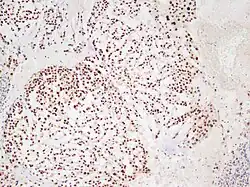

Chordome sind langsam und destruktiv wachsende Tumoren der Wirbelsäule und der Schädelbasis, die in etwa 10 % der Fälle metastasieren.

Chordome werden manchmal zu den Knochentumoren gezählt, obwohl sie nicht aus Knochengewebe stammen, sondern aus Resten der Chorda dorsalis (Notochordoa) an den Enden der Wirbelsäule. Damit lassen sich auch ihre Hauptlokalisationen, nämlich Schädelbasis und Steißbein, erklären. Die ICD-O-3 klassifiziert sie unter die Sonstigen Tumoren des Nervensystems (Nr. 937).